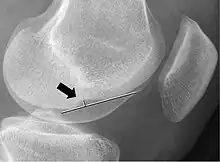

Measurement technique to determine the depth of the femoral notch on lateral x-rays

In radiology, the deep lateral femoral notch sign is a finding on a lateral radiograph that is considered an indirect sign of a torn anterior cruciate ligament (ACL).[1][2] It is an abnormal deepening of the lateral condylopatellar sulcus from an osteochondral impaction fracture.[1][3] A depth greater than 1.5 mm is a reliable sign of a torn ACL.[1]